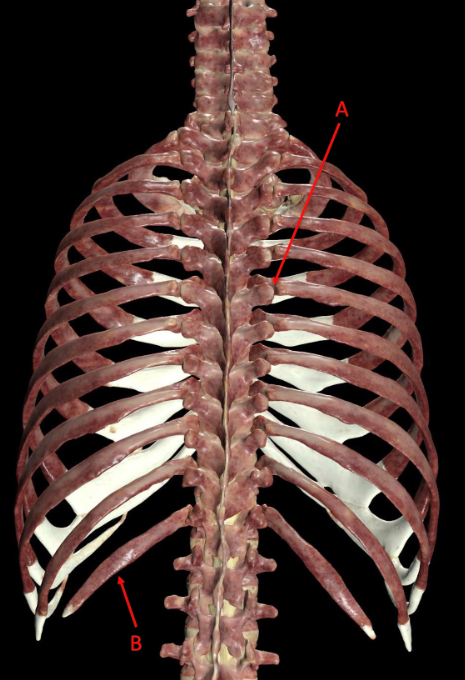

A. manubrium, point of attachment for muscles and bones, protection of heart and vital organs

B. Costochondral joint, surfaces of attachment for anterior muscle fibers